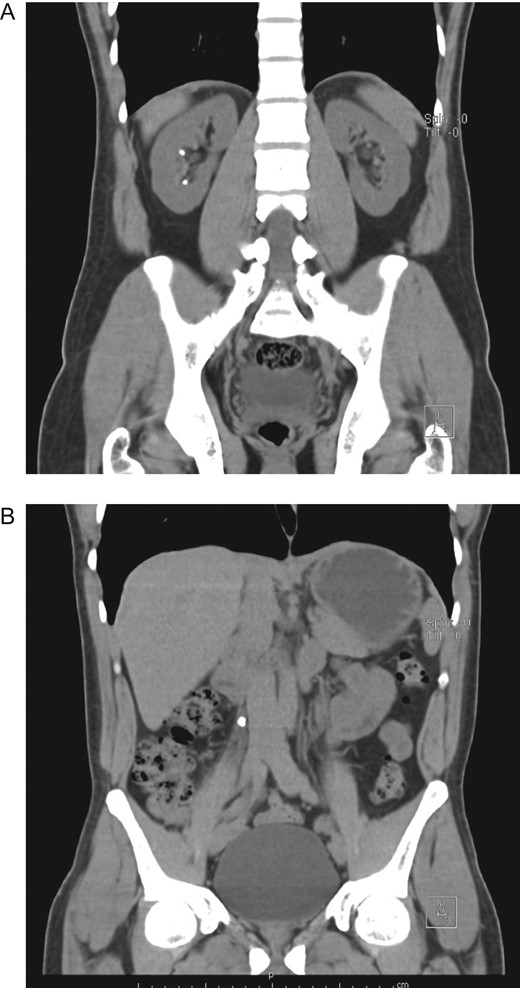

After adequate resuscitation and analgesia, his pressure and vital signs were stabilized, laboratory exams did not reveal leukocytosis or anemia however his hemoglobin (Hb) level decreased 4 points from 18 to 14 g/dl. He was admitted for close surveillance and under continuous monitoring. During hospitalization, the patient remained stable without tachycardia or episodes of hypotension, his urinary output was normal and his pain disappeared. However, 48 h after admittance, a new CBC revealed a Hb of 10 g/dl, a new CT was performed and the liver hematoma had grown ~50% (Fig. 3A and B), yet as the patient remained stable, non-operative management of his liver hematoma was decided.

(A) Contrast-enhanced CT, subcapsular liver hematoma 48 h after admittance. (B) Contrast-enhanced CT, the liver hematoma had grown ~50%.